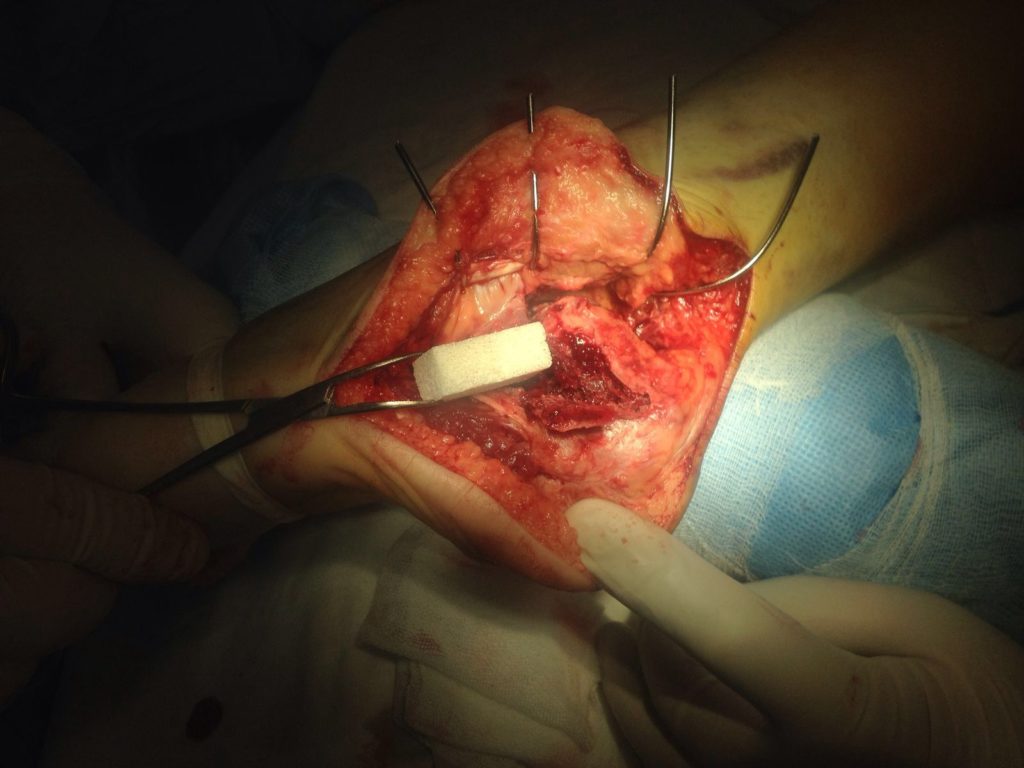

Применение материала Остеоматрикс при импрессионно-оскольчатом переломе пяточной кости

Операция – открытая репозиция, остеосинтез пяточной кости пластиной с костной ксенопластикой материалом «Остеоматрикс». На контрольных снимках в три месяца имеется консолидация перелома, миграции фиксатора нет, имеется остеоинтеграция ксенопластического материала.